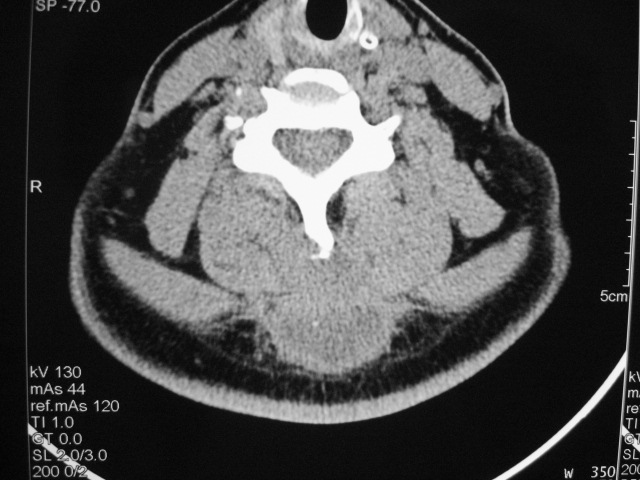

女,46岁,发现颈后区肿块3月余.

颈后软组织肿块,内可见坏死区及点状钙化,邻近颈椎棘突可见破坏,邻近肌间隙模糊,肿块周围脂肪间隙可见索条状影。

考虑:1)感染,结核可能;

2)肿瘤不能排除。